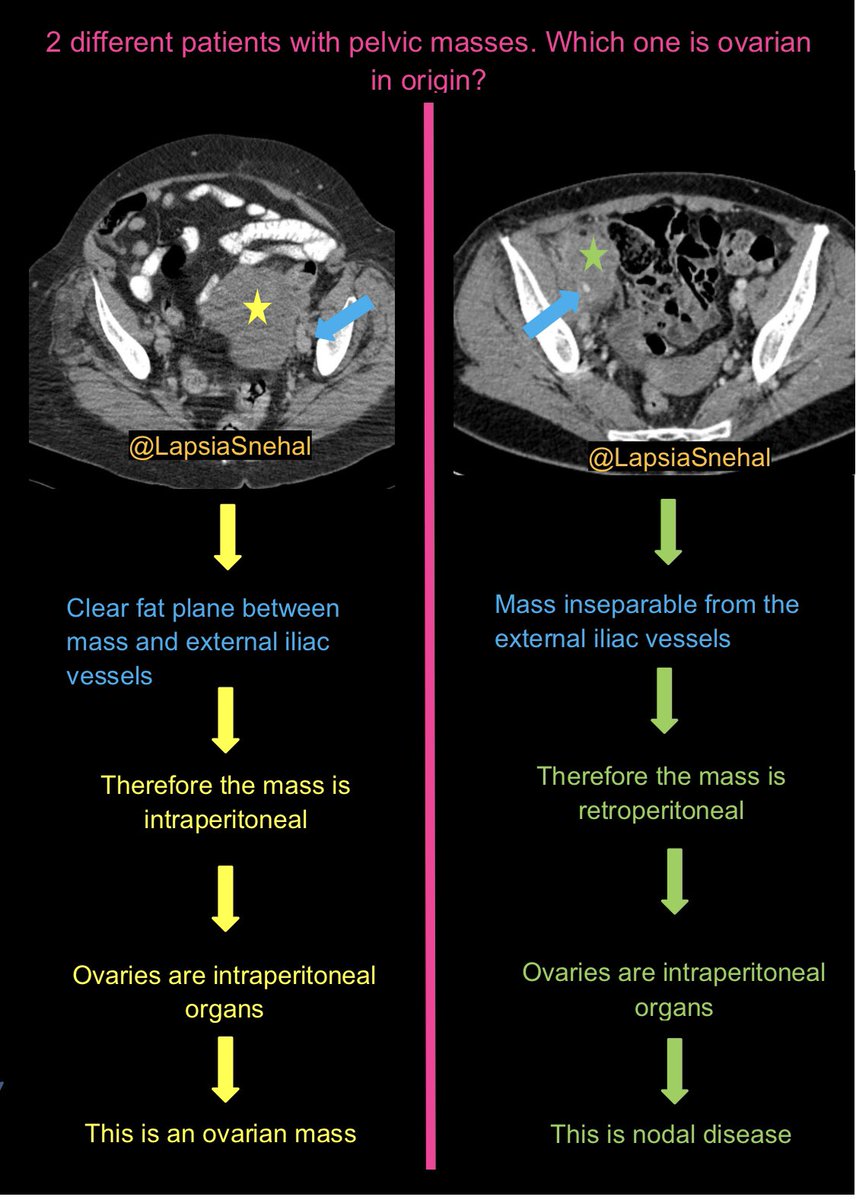

Pelvic masses can cause diagnostic uncertainty. This tip may help. #FOAMrad #FOAMed #meded #radres #futureradres #medstudenttwitter #gitwitter #anatomy #frcr #surgery #radiology #radtwitter #medtwitter #gyn #obygyn #abdrad